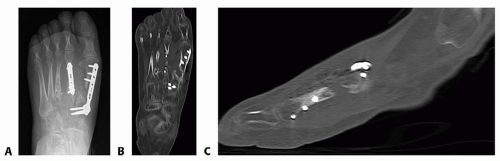

Plain weight-bearing radiographs of the foot and/or ankle are necessary for complete evaluation (FIG 3A).

Other imaging studies may be helpful. MRI may show extent of infection or the presence of avascular necrosis. CT scans confirm nonunion and show bone quality and structural bone loss, bony defects and deformities (FIG 3B,C).

FIG 3 • A. Anteroposterior radiograph of nonunion of the first metatarsal. Axial (B) and sagittal (C) CT scans confirming the nonunion.